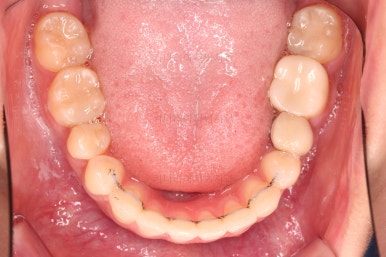

마찬가지로 초진 시 입안의 모습입니다.

입안 사진을 보니 문제점이 보이죠.

바로 어금니가 없는 상태였습니다.

틈이 다 없어졌고, 교합도 양호합니다.

무엇보다 임플란트 없이 결손부위가 깔끔하게 채워졌고요.

매우 다행으로 사랑니도 다 있었기 때문에 마치 큰 어금니가 다 있는 것과 같은 상황이 되었습니다.

입안의 모습은 더할나위 없이 잘 개선되었고요.

상하좌우 이 뽑은 위치와 크기가 달라 이정도 중앙선은 매우 잘 맞는 상황인거고요.